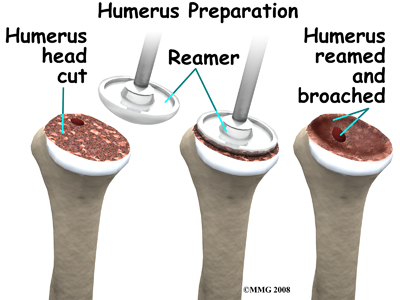

At this point, the surgeon can prepare the bone for attaching the replacement parts. The ball portion of the humeral head is removed with a bone saw. The hollow inside of the upper humerus is prepared using a rasp, which allows your surgeon to mold the space in order to anchor the metal stem of the humeral component inside the bone.